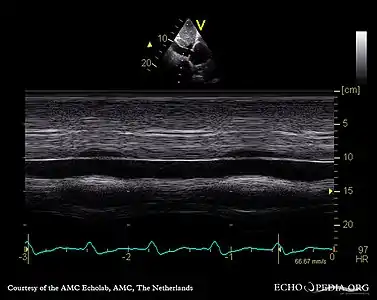

Echocardiogram: severe TR